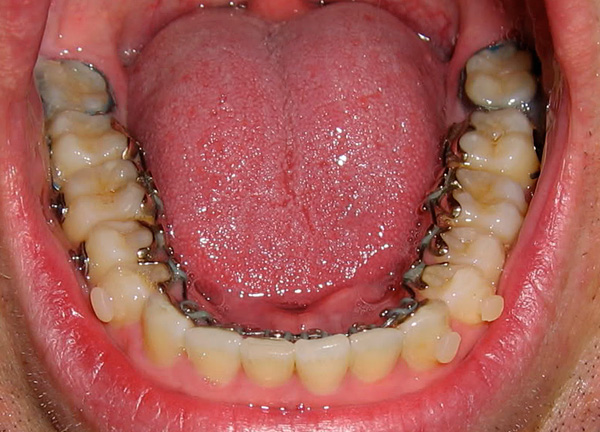

- Trattamento ortodontico. Oggi, la tattica di un ortodontista prima di mettere in scena gli stessi sistemi di staffe per rimuovere i denti del giudizio, specialmente quelli che, se non tagliati, si appoggiano ai vicini sette, come se spingessero l'intera dentatura, ha guadagnato popolarità. Gli studi hanno dimostrato che ciò è giustificato, poiché il successo della correzione del morso mantenendo i denti del giudizio interferenti è dubbio. Tuttavia, non è sempre necessario rimuovere gli otto durante l'installazione delle parentesi graffe.